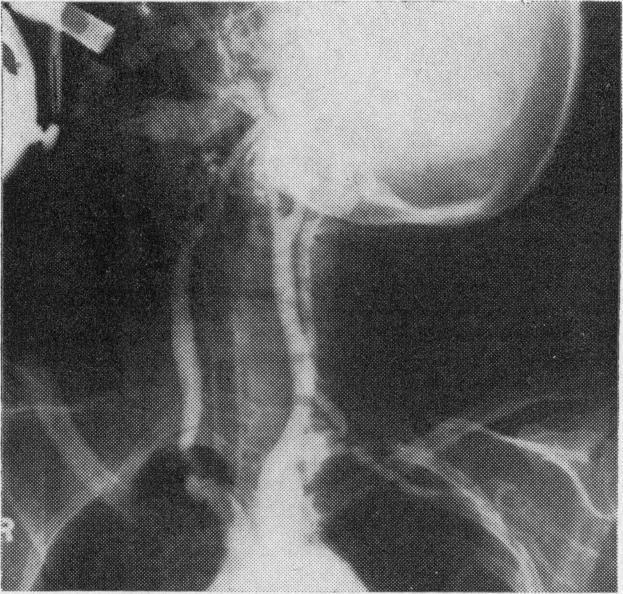

Pulseless disease with optic atrophy, aortic incompetence and recurrent peptic ulceration.

https://cdn.ncbi.nlm.nih.gov/pmc/blobs/56fb/1864418/4d774952bc1f/procrsmed00037-0089-a.jpg